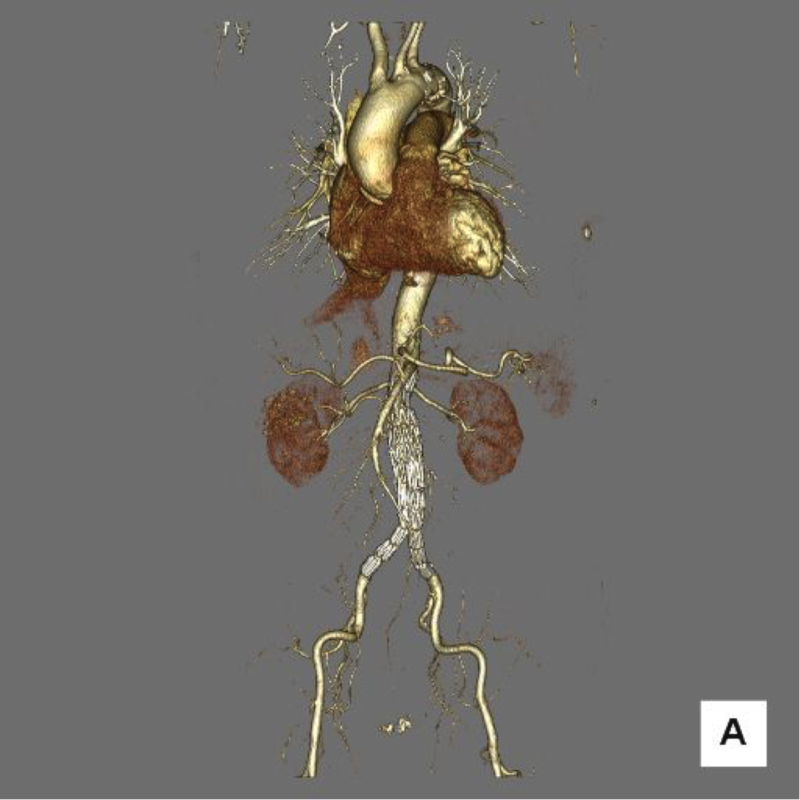

大動脈とは、体のなかでもっとも太い血管であり、全身に血液を送り出す動脈の幹です。お腹に位置する大動脈の直径は通常2㎝ほどです。その大動脈の一部が直径3㎝以上の瘤状に膨れたものを、腹部大動脈瘤といいます。腹部大動脈瘤の多くは、腎動脈*よりも下の位置に発生します。

腹部大動脈瘤の形には、大きく紡錘状瘤と嚢状瘤の2種類があります。下の図のように、紡錘状瘤とは大動脈が紡錘状の瘤になったものです。嚢状瘤とは大動脈瘤の一部が飛び出すように瘤になったものです。

嚢状瘤は紡錘状瘤よりも局所的に圧力がかかっているため、破裂しやすいといわれています。しかし、破裂する確率は形だけでなく直径も大きく関係しています。たとえば、瘤の直径が5㎝を超えると破裂する確率が高くなります。その場合、瘤の形状に関わらず、早急に治療を受けることをおすすめします。

ステントグラフトとは人工血管にステントという金属でできたバネを取り付けたもので、腹部大動脈瘤のなかにこのステントグラフトを挿入し留置することで瘤のなかに血液が流入することを防ぐ治療法をステントグラフト挿入術といいます。

まず、カテーテル(医療用の管)を血管のなかに挿入するため、脚の付け根にある大腿動脈を3㎝から4㎝の皮膚切開で露出します。その後、大腿動脈からカテーテルを腹部大動脈瘤まで進めていき、ステントグラフトを瘤の内部に留置します。